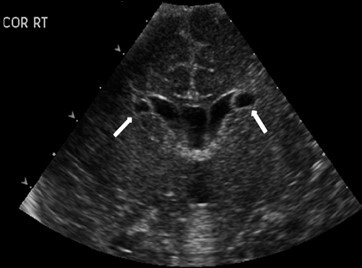

Neonatology Cyst 1 Image